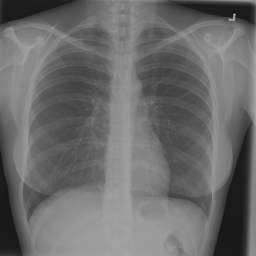

Figure 2: Examples of normal vs. abnormal images of considered datasets. Natural images: (first row) cars vs other classes of CIFAR10 dataset [1], (second row) digits “0” vs digits “1” – “9” of SVHN dataset [2]. Medical images: (third row) healthy tissue vs. tissue with metastases in H&E-stained lymph nodes images from Camelyon16 challenge [3], (fourth row) normal chest X-rays vs. chest X-rays with abnormal findings from NIH dataset [4].

Anomaly detection is a crucial task in the deployment of machine learning models, where knowing the “normal” data samples should help spot the “abnormal” ones [5, 6]. If an input deviates from the training data substantially (e.g., the input belongs to a class not represented in the training data), it is usually impossible to predict how the model will behave [7, 8]. This trait is especially important in high-consequence applications, such as medical decision support systems, where it is especially vital to know how to recognize the anomalous data. Identification of rare occurrences is another important application where anomaly detection is useful. For example, in pathology, where labeling diverse microscopy datasets is both time-consuming and expensive, the rare types of cells and tissues require specialized expertise from the annotator [9, 10]. Forthright anomaly classification and segmentation algorithms are typically prone to mistakes either because of the lack of sufficient annotation (thousands of labeled examples needed for supervised models) or because of the lack of representative data altogether (e.g., the case of some rare pathologies). Moreover, these algorithms are affected by the need to deal with very unbalanced and apriori noisy data, frequently leading to inaccurate results (e.g., the findings on chest x-rays can be so subtle that they can lead to disagreement in the interpretation [11, 12]). Because the normal cases greatly prevail over the abnormal ones, the anomaly detection could alleviate the annotation burden by automatically pointing to the rare samples.

In recent years, deep learning techniques achieved important advances in image anomaly detection [13, 14, 15, 16, 17, 18, 19, 20, 21]. However, these efforts were primarily focused on artificial problems with distinct anomalies in natural images (e.g., outliers in images of “cars” in the CIFAR10 dataset [1], see Figure 2). The medical anomalies, however, differ from those in the natural images [15, 19, 22]. Contrary to the natural images, the anomalies in the medical domain tend to strongly resemble the normal data. For example, detection of obscure neoplasms in chest X-rays [4] and of metastases in H&E-stained lymph node images [3] manifest a blatant challenge at hand, with the anomalous tissues being barely different from the normal ones (see Figure 2). Although deep learning has proved useful for a variety of biomedical tasks [23, 24, 25, 26], only recently, a few groups started dedicating their effort to the anomaly detection problem [15, 19, 27]. However, to the best of our knowledge, a thorough comparison of the state-of-the-art (SOTA) solutions in the medical domain is still missing despite the pressing demand and the prospective clinical value.

Anomaly Detection on Chest X-Rays

Chest X-ray is one of the most common examinations for diagnosing various lung diseases. We considered the task of the recognition of fourteen findings, such as Atelectasis or Cardiomegaly, on the chest X-rays in the NIH dataset (ChestX-ray14 dataset) [4] (Figure 2). Searching abnormalities on a chest x-ray is challenging even for an experienced radiologist since abnormality may occupy only a small region of lungs, or be almost invisible. The dataset consists of 112,120 frontal-view images of 30,805 unique patients: 86523 for training, 25595 for evaluation. We split the dataset into two sub-datasets having only posteroanterior (PA) or anteroposterior (AP) projections, because organs on them look differently. We tried different preprocessing during the hyperparameter search: rescaling to 256x256, 128x128, and 64x64 and histogram equalization, central crop (3/4 of the image size) to delete “noisy” borders. We considered images without any disease marker as “normal” and used them for training. Abnormal images for hyperparameter searching comprised of the training images of the most frequent disease (‘Infiltration’) out of fourteen possibilities. We also evaluated model on subset containing “clearer” normal/abnormal cases (provided by  [22]). This subset consists of 4261 normal images for training, 849 normal and 857 abnormal images for validation, and 677 normal and 677 abnormal images for testing.

Figure 6: Examples of normal (left) and anomaly (right) images of H&E-stained lymph node of Camelyon16 challenge [3] (top) and chest X-rays of NIH dataset [4] (bottom). We also showed the predicted anomaly score by the proposed method. The higher the score, the more likely to be an anomaly. Notice how the proposed method spots even the borderline cases.